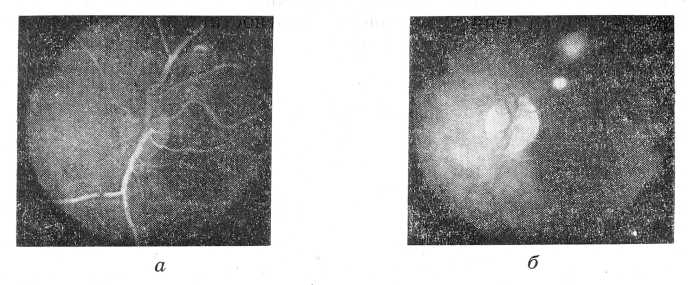

Рис. 1. Флюоресцентная ангиограмма больной Н., 17 лет.

а—артериальная фаза. Очаг начал светиться; б — венозная фаза. Флюоресценция очага уменьшилась.

Методом флюоресцентной ангиографии у 29 обследованных больных с атипичной картиной глазного дна выявлен дистрофический характер заболевания. Для этой группы пациентов характерным было появление флюоресценции патологического очага в ранней артериальной фазе (рис. 1, а), а у 3 больных она обнаружилась еще раньше — в хориоидальной фазе.

Границы очагов были четкими, хотя интенсивность свечения в различных участках очага неодинаковая. Уже в венозной фазе флюоресценция очагов заметно уменьшается (рис. 1, б) и почти сразу исчезает, как только контраст покинет сосуды сетчатки. У 3 указанных пациентов свечение очагов держалось 2—3 мин. после исчезновения флюоресцеина из сосудов. Однако весь комплекс флюоресценции — раннее появление, четкость границ, угасание в венозной стадии — дал основание рассматривать ее как признак дистрофических изменений. Эффективность лечения, направленного на нормализацию обменных процессов (улучшение остроты зрения, уменьшение абсолютной скотомы) подтвердила правильность трактовки характера процесса.